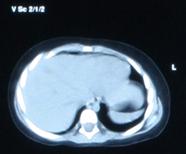

Fig. nr. 270. Formatiunea tumorala explorata echo in figura anteorioara, acum la computer tomografie, in raport cu ficatul. Intraoperator s-a gasit un teratom retroperitoneal.